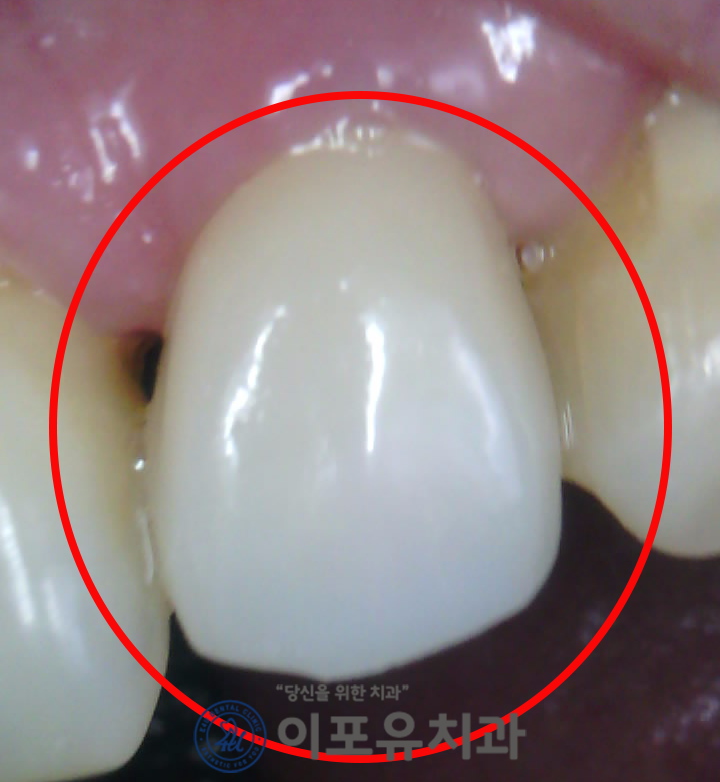

엔도 완료된 모습인데요.

아무래도 앞니는 심미적인 요소를

많이 받는 치아이다 보니

치아 색깔을 결정하는데

신중할 수밖에 없습니다.

전치부 보철 역시

인접 자연치와 유사한 색깔의

지르코니아를 택하는 것이 좋은데요.